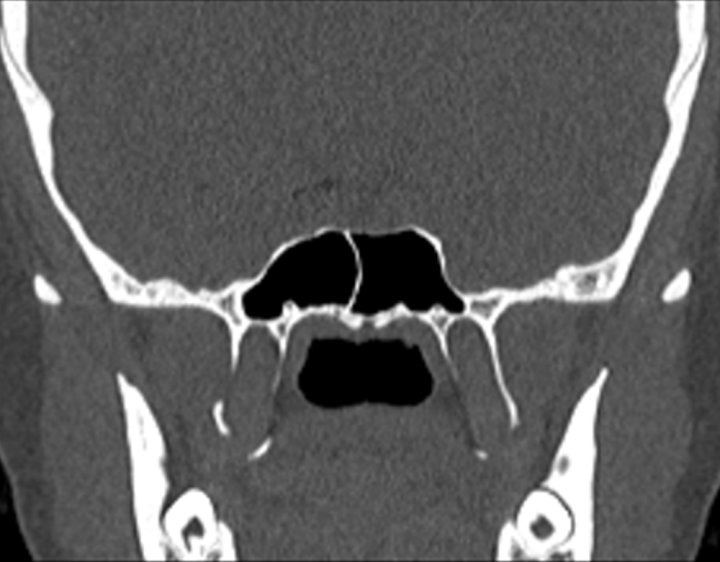

Click any image for labels.